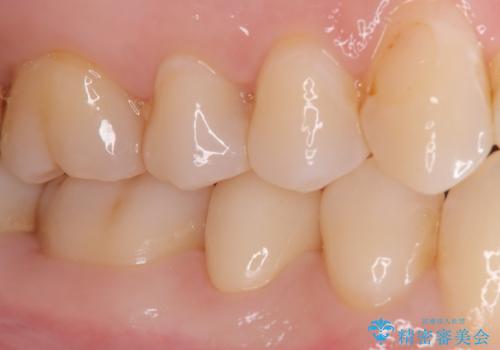

虫歯の部分のみを慎重に削除し、できる限り健康な歯質を残すように配慮しました。その後、強度があり適合性の高いセラミッククラウンを装着し、機能性と審美性の両方を確保。セラミックは変色しにくく、長期的な再発リスクも低減できるため、患者様にも安心していただけました。定期検診を継続することで、今後の虫歯リスクも管理していきます。